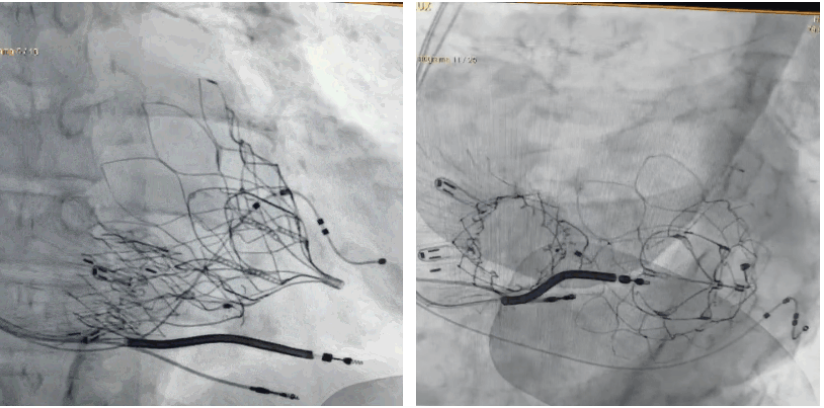

術(shù)后DSA顯示Lux-Valve Plus與Tendyne和ICD無(wú)相互影響

手術(shù)在全麻狀態(tài)下進(jìn)行。術(shù)者采用經(jīng)右側(cè)頸靜脈入路的方式將輸送器送入患者心臟內(nèi),在TEE及DSA引導(dǎo)下調(diào)整輸送器頭端角度,使得輸送器與三尖瓣瓣環(huán)平面垂直。在輸送器進(jìn)入右心室后釋放室間隔錨定裝置,而后釋放瓣葉夾持件(2個(gè)耳片結(jié)構(gòu))成垂直狀態(tài)。在TEE及DSA確定夾持件固定至三尖瓣葉根部且位于右室側(cè)后釋放人工瓣心房側(cè)盤片。隨后調(diào)整瓣膜同軸性以及室間隔錨定件位置(貼合室間隔),前推藏針管并固定,進(jìn)而釋放室間隔錨定裝置,并再次確認(rèn)瓣膜位置、穩(wěn)定性及同軸性,合攏輸送鞘后撤出輸送器,完成LuX-Valve Plus人工三尖瓣瓣膜的植入,僅殘余微量瓣周漏。且經(jīng)手術(shù)中心電生理團(tuán)隊(duì)評(píng)估,病人的起搏器和ICD功能沒有受到影響。